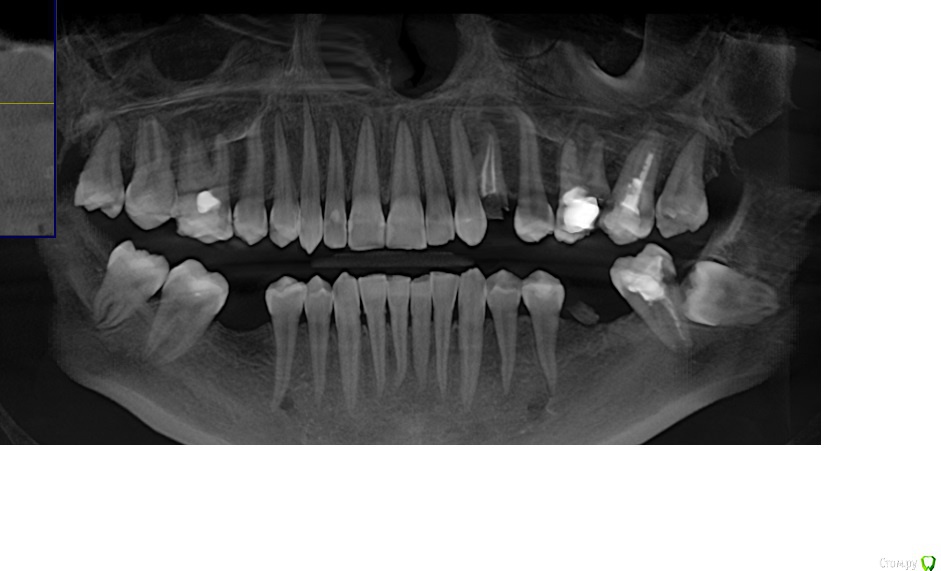

Doctor Vlad Опубликовано 31 января, 2016 Поделиться Опубликовано 31 января, 2016 здравствуйте!зуб 24 и корешок 36 удалены ранее 2 мес назад, слева: и верх и низ молярная группа сохранению не подлежит! 26 ниже уровня кости разрушен... карман между 26 и 27 до верхушки. 7 подвижна слегка. пациент хочет имплант в 24 первоначально. удалять жевательную группу пока не хочет но протезировать будет на имплантах.мои мысли: поставить 24 да пусть он там приживается месяца 3. тем временем удалить верх 26 27 кюретаж засыпать БИООС для сохранения высоты кости мембрана зашить. 28 как стенка дефекта пусть постоит) по заживлению верха удаление низ 37 38. через 3 месяца импланты в области 26 и 36.. чз месяца 3 одновременно запротезировать 24 26 36 и ввести в функцию.не стоит отдельно перегружать 24, лучше уговорить на одномоментную нагрузку? сильно перегрузиться правая сторона за время отсутствия левой? ваше мнение? альтернативные варианты.. предложения)? Ссылка на комментарий